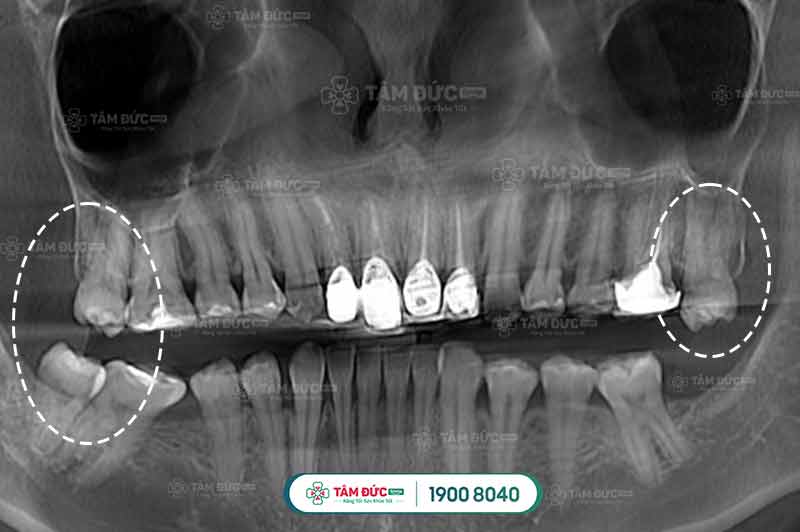

Trường hợp răng khôn của Quý khách mọc thẳng

1.1. Răng khôn của Quý khách mọc thẳng

Có nhiều nguyên nhân dẫn đến tình trạng đau nhức như: viêm nha chu, viêm nướu, viêm tủy răng. Với những trường hợp này bác sĩ sẽ chỉ định nhổ bỏ đi chiếc răng khôn của Quý khách. Còn nếu như tình trạng răng của Quý khách đang ở mức độ nhẹ không ảnh hưởng gì quá nhiều đến sức khỏe thì không nhất thiết phải nhổ bỏ chúng.